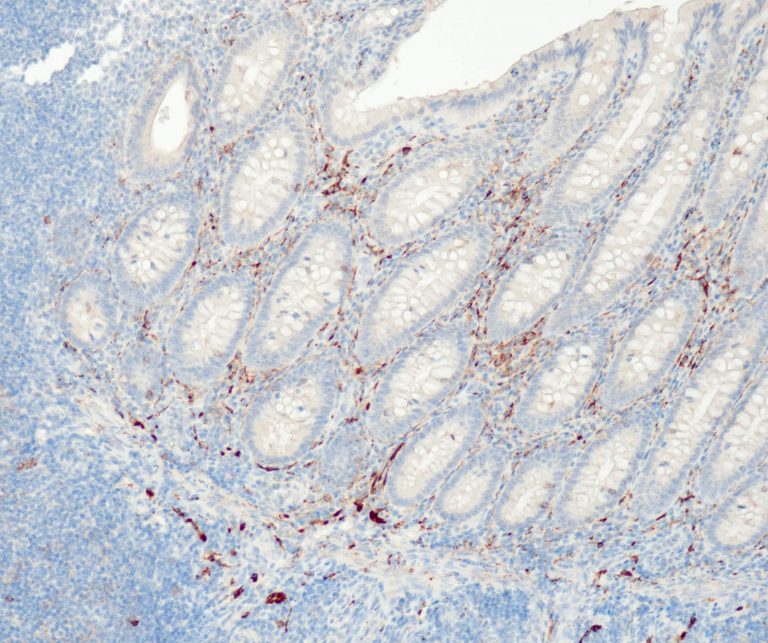

Gastrointestinal (GI) Pathology